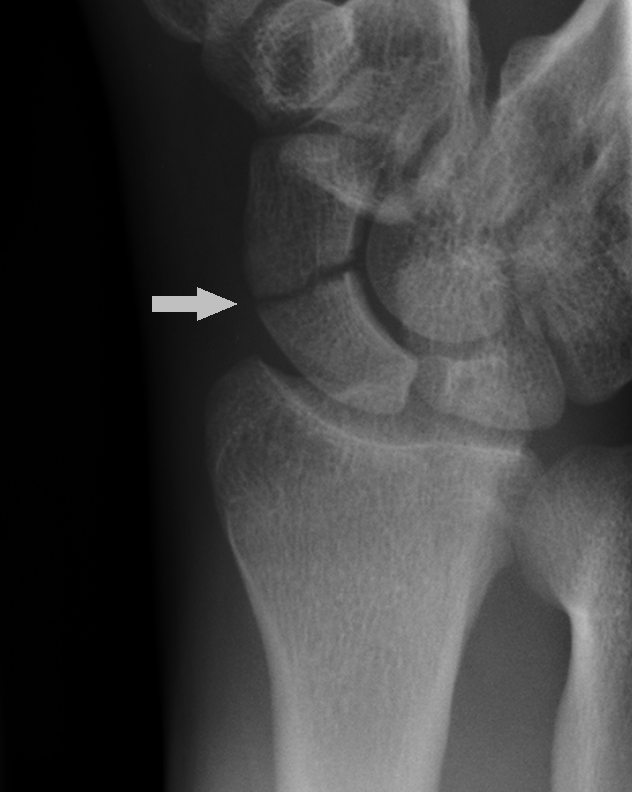

16. 테리 토마스 징후란 무엇인가?

주상월상간 해리는 주상골과 월상골 사이의 인대 파열의 결과로 나타난다. 손목의 전후영상(AP view)에서 주상골과 월상골 사이의 간격이 넓어져 있는 것으로 알 수 있으며, 테리 토마스 징후(Terry Thomas sign)로 알려져 있다. 참고로 테리 토마스(1911-1990)는 치아가 벌어진 영국 코미디 배우다.

△ Terry Tomas (이미지 출처 : http://www.radrounds.com/photo/terry-thomas-sign)

△ Terry Tomas (이미지 출처 : http://www.amazon.co.uk/)